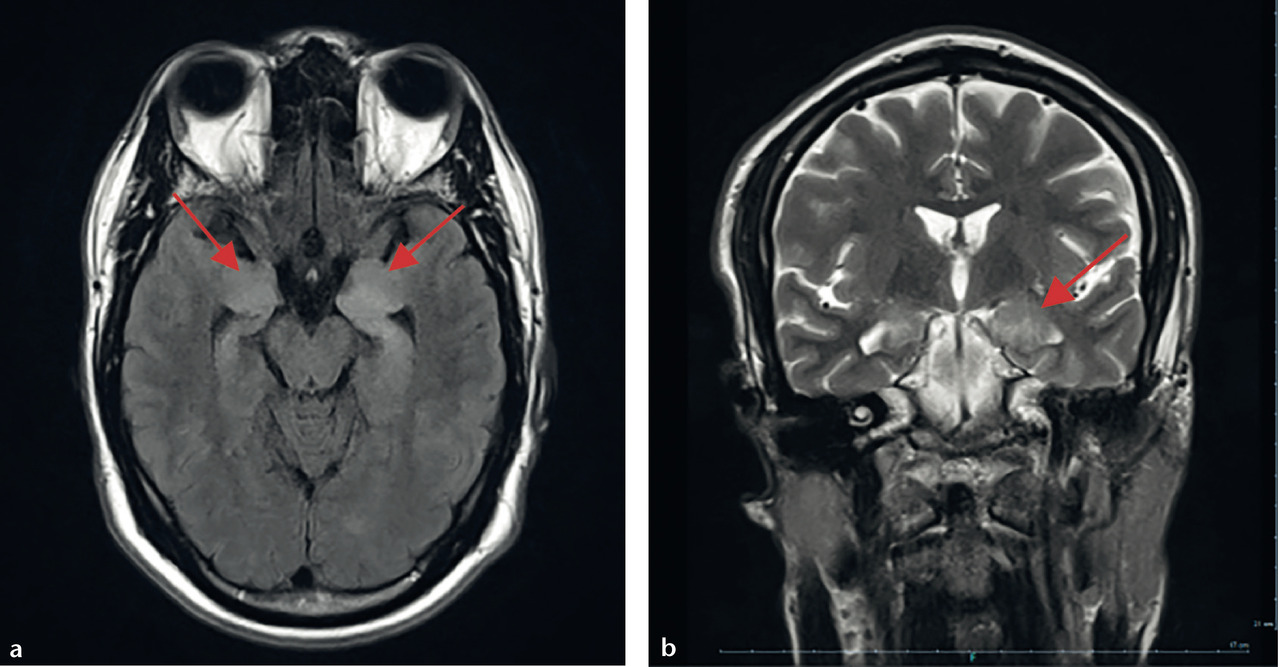

IRM. Troubles mnésiques d’apparition subaiguë chez un patient de 40 ans sans antécédents particuliers. Hypersignal FLAIR bilatéral temporal interne prédominant à gauche (flèche). a) Séquence axiale FLAIR. b) Séquence coronale T2.